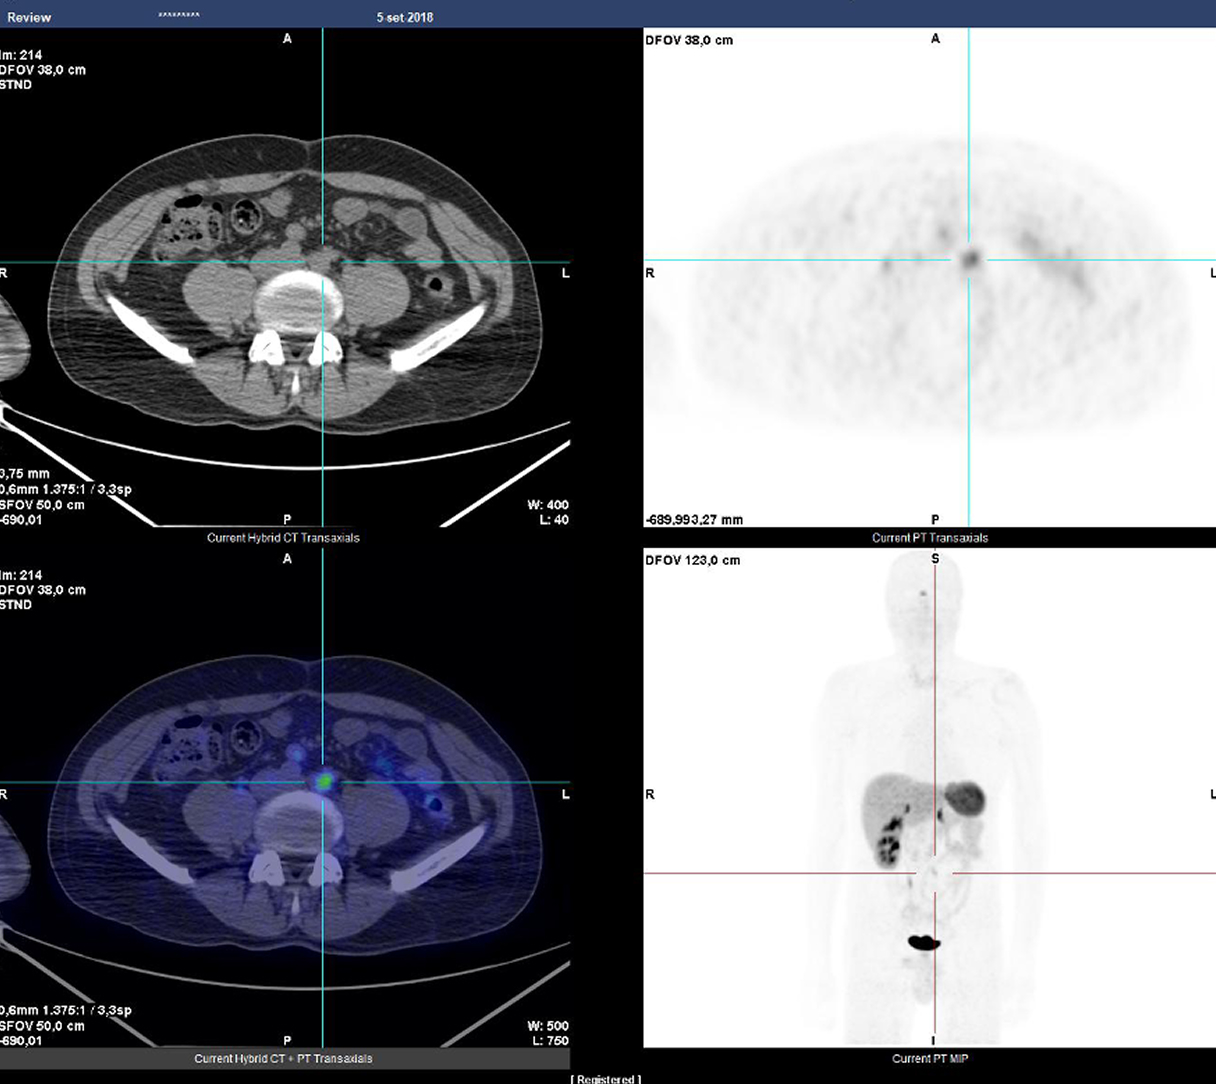

Caso condiviso da Saima Mushtaq

Paziente con anamnesi di malattia coronarica e pregresso impianto di stent sulla discendente anteriore sinistra.

Per prima cosa, esamina l'intera scansione. Concentrati sul tronco comune e sulla porzione prossimale della discendente anteriore sinistra.